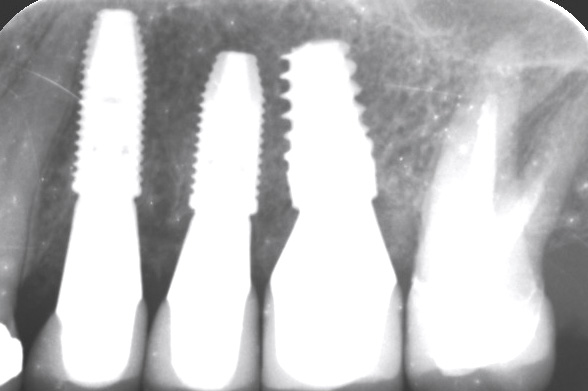

9/13 - Control x-ray image after implant placement

Multiple socket preservation in the maxilla with collacone® max – Dr. D. Jelušić